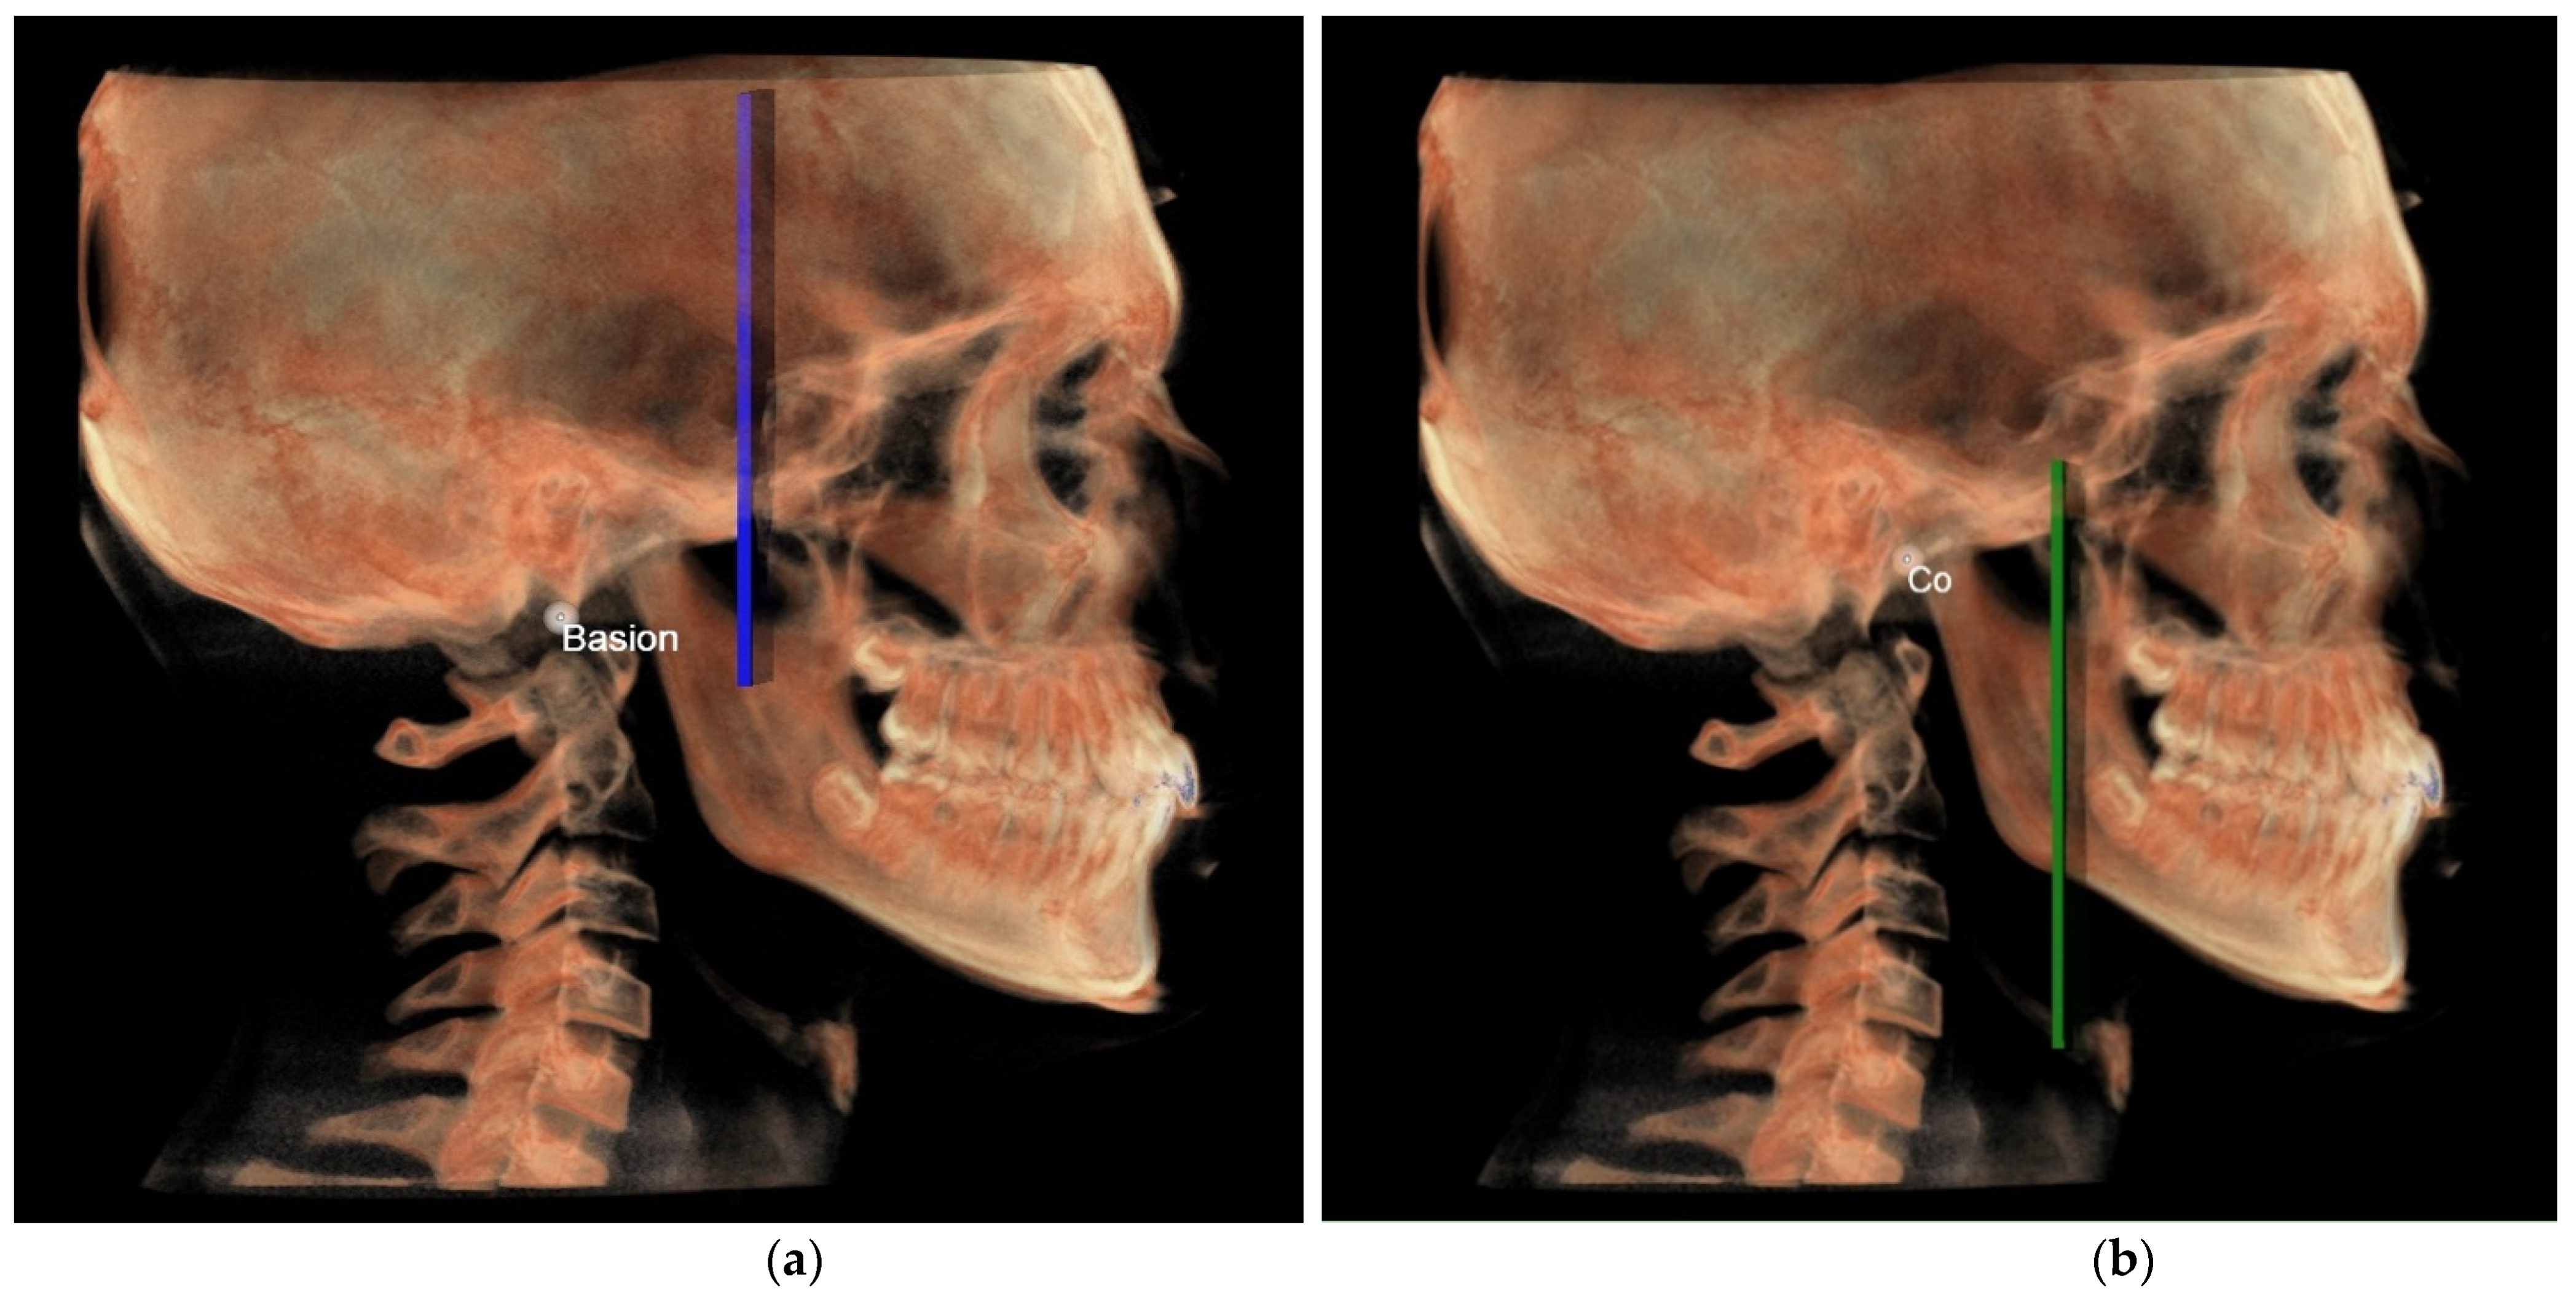

- Middle Cranial Floor (MCF) and Mandibular ramus (Figure 3): this parameter compares the horizontal dimension of the middle cranial floor (Ar to neutral PM) and the width of the ramus (Ar to ARa). These parameters were measured along the Ref.

- The middle cranial floor (Figure 10) was determined by the distance from Ba to a plane passing through the two anterior clinoid processes and normal to the axial plane. The anterior clinoid processes were chosen as they represented the most posterior point of the anterior cranial floor and the most anterior point of the middle cranial floor.

- The mandibular ramus was measured from the right and left condylion to a plane passing through the right and left lingual tuberosity and normal to the axial plane (Figure 10).